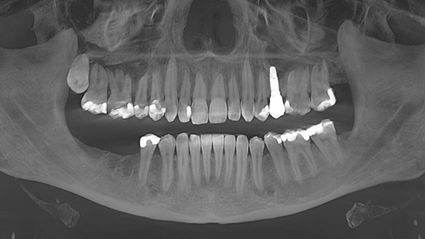

Meine Symptome, darunter Gelenkschmerzen, neurologische Probleme und Sehstörungen, nahmen trotz der Behandlung langsam aber stetig zu. Meine Symptome - vor allem die neurologischen - verschlimmerten sich, nachdem ich nach einem Zahnverlust und einer umfangreichen Wurzelbehandlung ein Titanimplantat erhalten hatte.